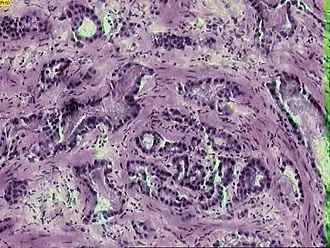

![]() Микрофотография инвазивной аденокарциномы простаты | |

Рак предста́тельной железы́ (рак проста́ты, карцино́ма проста́ты, карцино́ма предста́тельной железы́; англ. prostatic cancer, лат. adenocarcinoma prostatica) — злокачественное новообразование, возникающее из эпителия альвеолярно-клеточных элементов предстательной железы.

К В. Л. Бялику (1971) восходит следующая гистологическая классификация рака предстательной железы, по которой он подразделяется на следующие формы[11]:

- аденокарцинома (если рак возник из железистого эпителия);

Около 95 % случаев рака предстательной железы составляют ацинарные аденокарциномы; на долю же остальных видов аденокарцином (протоковая, муцинозная, мелкоклеточная, переходно-клеточная) приходится не более 5 %[12]